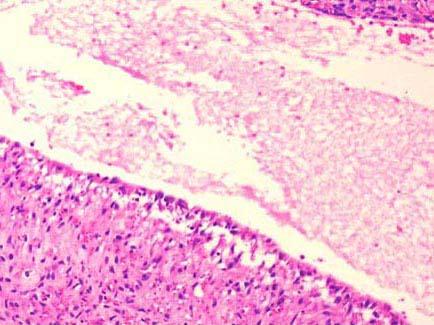

问题 患者,男,27岁,近日来声嘶伴吞咽疼痛,喉镜见声门上区有一灰白色囊状物,约1cm×0.6cm×0.5cm大小,活检镜下如图所示,正确的诊断是 ( )

选项 A.甲状舌骨囊肿 B.声带息肉 C.会厌囊肿 D.喉纤维瘤 E.喉神经纤维瘤

答案 C